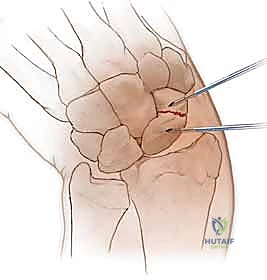

هذه هي التقنية المتقدمة التي يبرع فيها الأستاذ الدكتور محمد هطيف في صنعاء. بدلاً من فتح الرسغ، يتم إجراء العملية بأكملها من خلال شقوق دقيقة لا تتجاوز 2-3 مليمترات، تحت إرشاد جهاز الأشعة المرئية (Fluoroscopy) وبمساعدة المنظار المفصلي الدقيق.

العملية الجراحية بتقنية التدخل المحدود ليست مجرد "إدخال مسمار"، بل هي عمل فني وهندسي دقيق يتطلب مهارة جراحية فائقة، تخطيطاً مسبقاً، وتنسيقاً مثالياً بين يدي الجراح والصور الإشعاعية. يتبع الأستاذ الدكتور محمد هطيف بروتوكولاً صارماً لضمان أعلى معدلات النجاح.